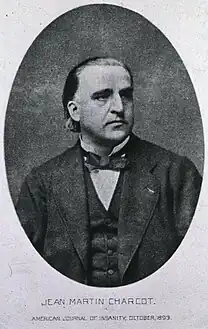

In 1817, James Parkinson published his essay reporting six people with paralysis agitans.[169] An Essay on the Shaking Palsy described the characteristic resting tremor, abnormal posture and gait, paralysis and diminished muscle strength, and the way that the disease progresses over time.[170][171] Early neurologists who made further additions to the knowledge of the disease include Trousseau, Gowers, Kinnier Wilson and Erb, and Jean-Martin Charcot, whose studies between 1868 and 1881 increased the understanding of the disease.[169] Among other advances, Charcot made the distinction between rigidity, weakness and bradykinesia.[169] He championed the renaming of the disease in honor of James Parkinson.[169]